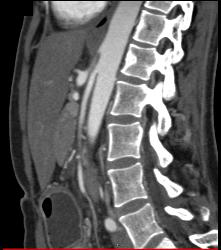

Superior Mesenteric Artery (SMA) Syndrome